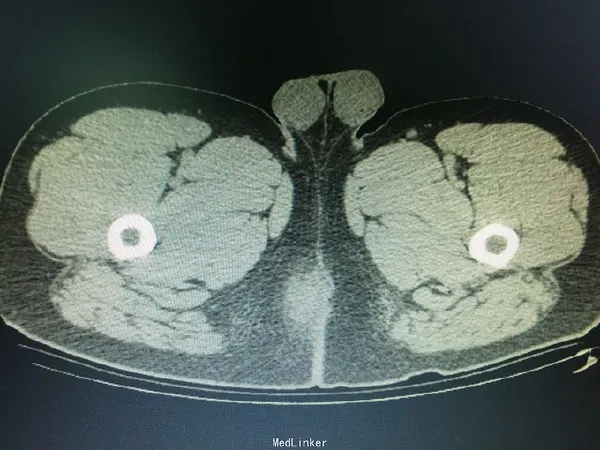

专业医生常利用直肠指诊这一方法,通过手触评估肛门直肠区的肿胀、硬结或波动感。同时,对于较深层病变患者可能疑义不明时,可联合影像学检测(如MRI或CT)以明确脓肿范围与解剖关系。